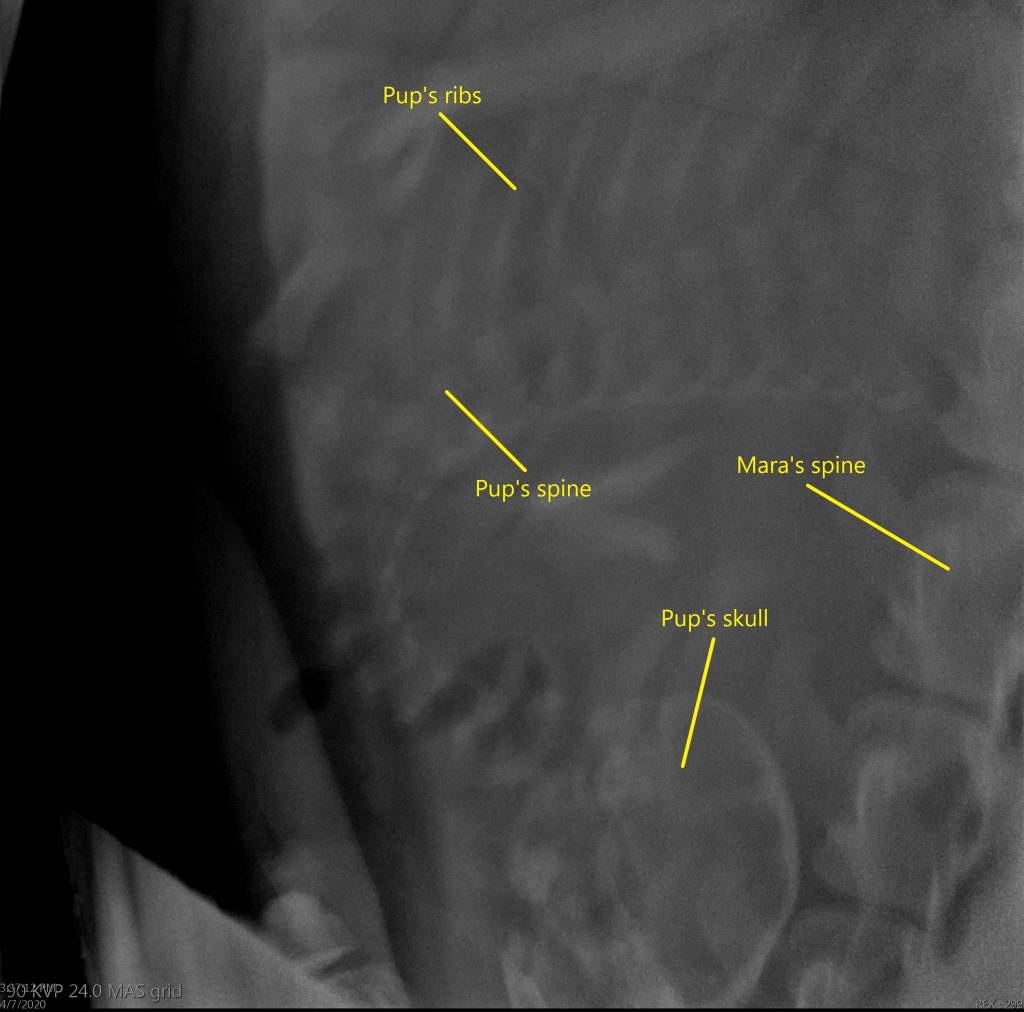

“Estimating a delivery date is imprecise in any species, but in Steller sea lions it is even harder since we have only tracked a few pregnancies,” Dr. Carrie Goertz, director of animal health at the SeaLife Center, said in a Thursday press release. “Nevertheless, I expect Mara to give birth earlier than all of our other births since I was able to detect the developing pup about a month before other cases.”

The study found that animals trained to voluntarily participate in health care had lower cortisol levels than animals that have to be restrained, so mammalogists at the SeaLife Center train Mara and other aquatic mammals to be familiar with medical equipment through frequent ultrasounds and radiographs in order to keep her stress levels low. Hartman said that is also accomplished by gradually introducing the equipment into the animals’ exhibits so that they eventually become desensitized to it.